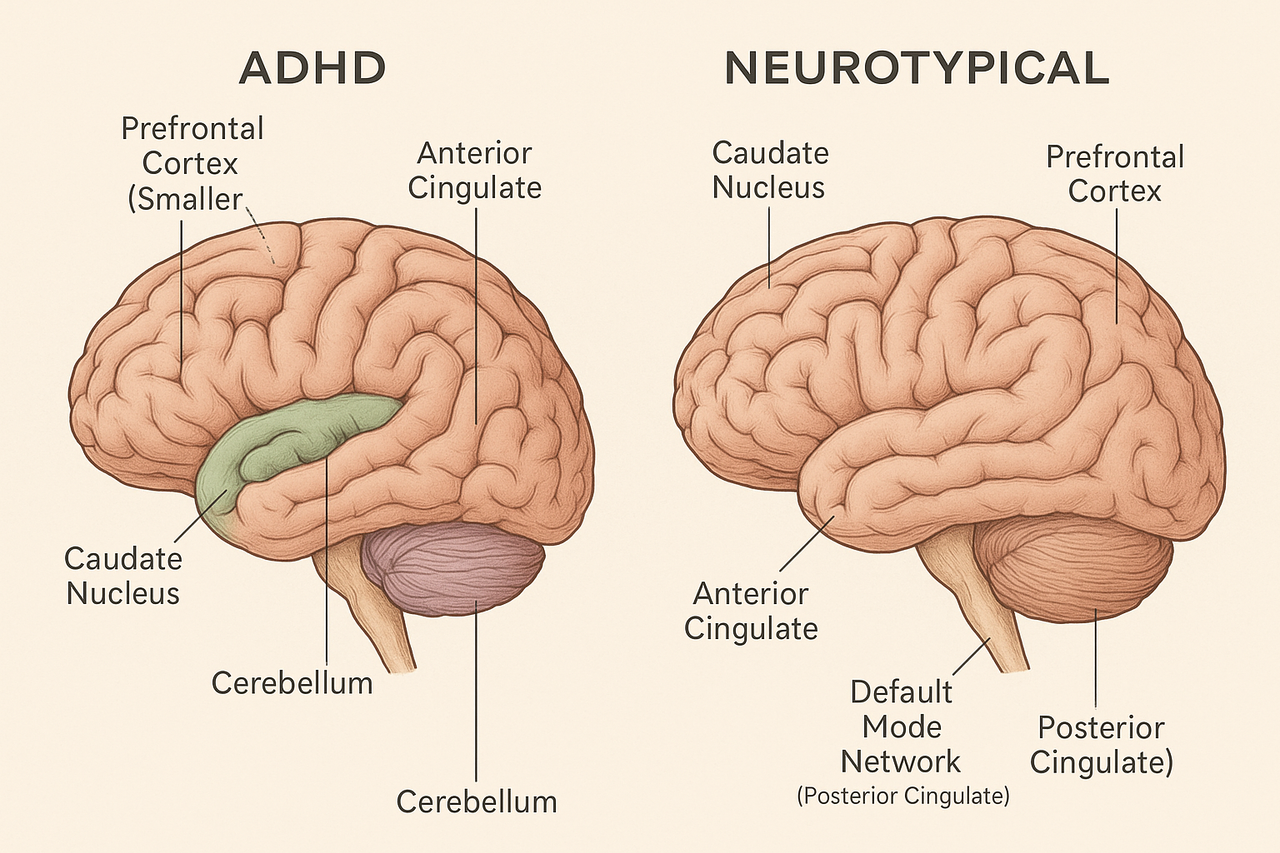

At the brain level, these symptoms reflect differences in the networks that govern executive function, impulse control and attention. Particularly in the prefrontal cortex, the region responsible for planning, decision-making and regulating behavior, and its connections with deeper regions like the striatum.

Put simply, the prefrontal cortex is like the planner and regulator, while the striatum is like the motivator and reward-seeker. When their communication is off balance, it can contribute to the challenges seen in ADHD. A PET scan can illustrate the difference between a brain with ADHD (left) and one without (right).